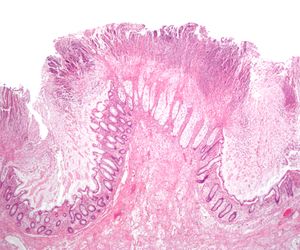

전신 항생제, 특히 광범위 항생제 (페니실린/세팔로스포린, 플루오로퀴놀론, 클린다마이신) 사용은 장의 정상적인 미생물총을 변화시킨다.[44] 항생제가 장내의 다른 경쟁 세균을 죽이면, 살아남은 세균은 공간과 영양분을 놓고 덜 경쟁하게 된다. ''클로스트리디움 디피실''은 이러한 세균 중 하나로, 장에서 증식하는 것 외에도 독소를 생성한다. 독소 A 또는 독소 B가 없으면, ''C. difficile''은 장에 집락할 수 있지만 위막성 대장염을 일으킬 가능성은 낮다.[44] 심각한 감염과 관련된 대장염은 염증 반응의 일부이며, "위막"은 염증 세포, 피브린, 괴사 세포의 점성 집합체에 의해 형성된다.[45]

''C. difficile'' 독소를 검출하는 검사가 나오기 전에는, 결장경 검사나 S상 결장경 검사를 통해 진단하는 경우가 많았다. 결장 또는 직장 점막에서 "가성 막"의 출현은 이 질환을 시사하지만, 진단적인 것은 아니다.[46] 가성 막은 염증성 잔해물과 백혈구로 구성된 삼출물로 이루어져 있다. 현재도 결장경 검사 및 S상 결장경 검사가 사용되기는 하지만, 현재는 ''C. difficile'' 독소 존재 여부를 검사하는 대변 검사가 진단의 첫 번째 단계로 자주 사용된다. 일반적으로 독소 A와 독소 B 두 가지만 검사하지만, 이 균은 다른 독소도 여러 개 생성한다. 이 검사는 100% 정확하지 않으며, 반복 검사에도 위음성률이 상당하다.[47]

가성 막성 대장염은 1978년, ''C. difficile'' 감염의 합병증으로 처음 기술되었으며, 가성 막성 대장염 환자로부터 독소가 분리되고 코흐의 가설이 충족되었다.[220]